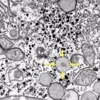

What is the organelle shown within the 4 yellow arrows?

peroxisome